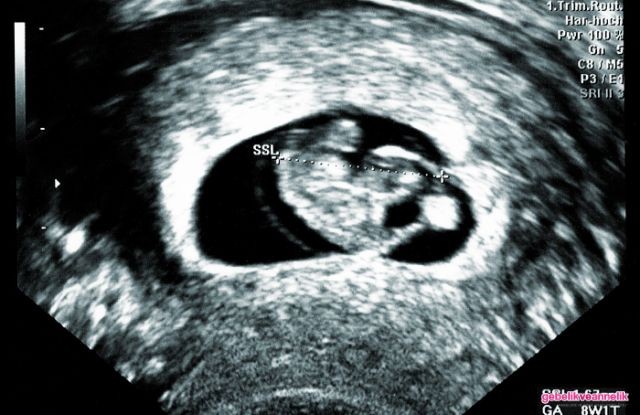

8. Hafta Anne Karnı Bebek Ultrason Görüntüleri